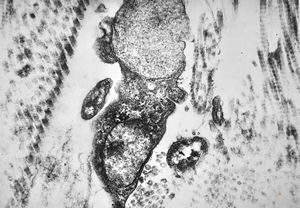

M, 17y. | sea-blue histiocyte syndrome - kidney